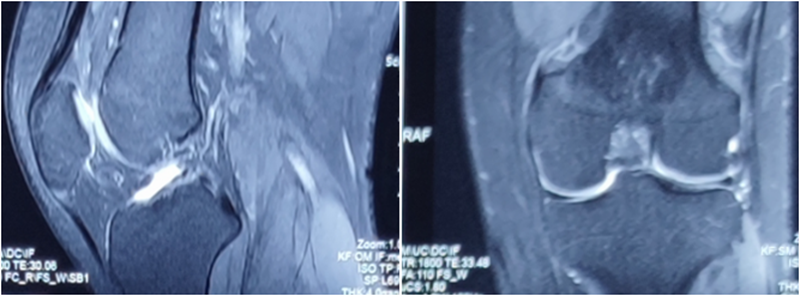

MRI检查评估ACL-R术后——韧带连续性信号好、方向好、愈合快,没有Cyclops综合征。

典型病例,张X,男,18岁,因扭伤致左膝关节疼痛伴活动受限1月余入院。

诊断:1.左膝前交叉韧带损伤;2.左膝外侧半月板损伤合并囊肿。

术前MRI

术后MRI